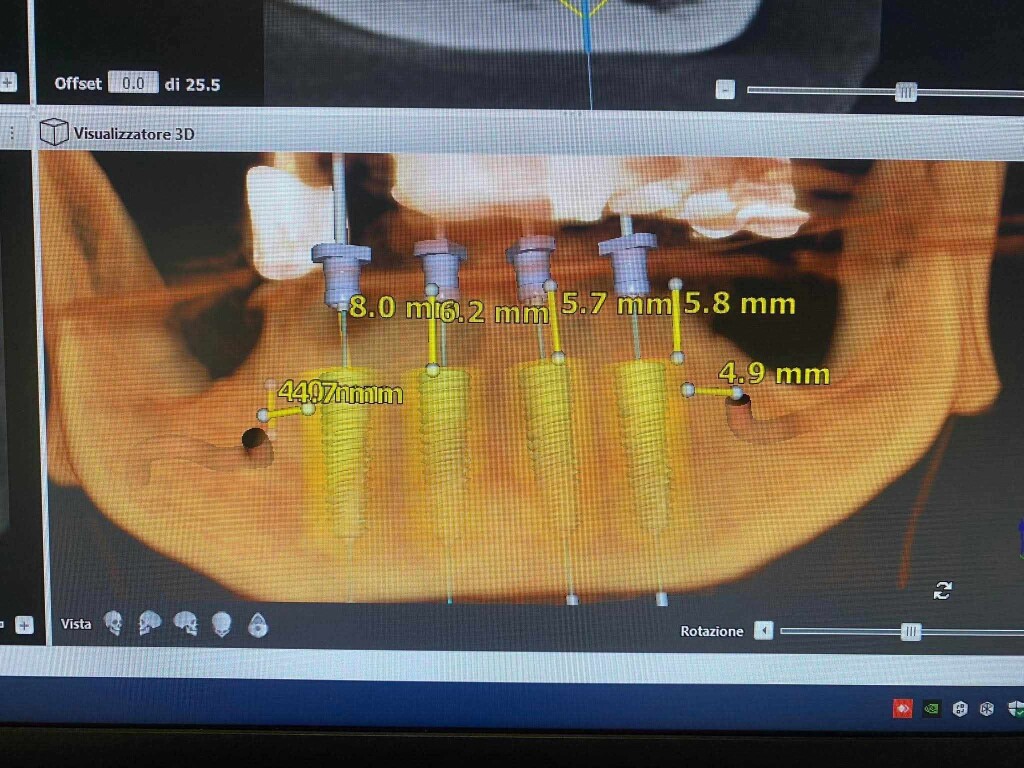

Per essere il più efficace possibile, ho pensato di stampare la CBCT ed eseguire sul modello l’intervento di All-on-4, facendo alcune considerazioni sull’osteotomia e sul posizionamento degli impianti.

e questa la progettazione ipotizzata dal collega.

La sua domanda era se effettivamente l’unica soluzione fossero due impianti dritti intraforaminali, con emergenza nella zona dei canini.

La mia risposta è no… vediamo.